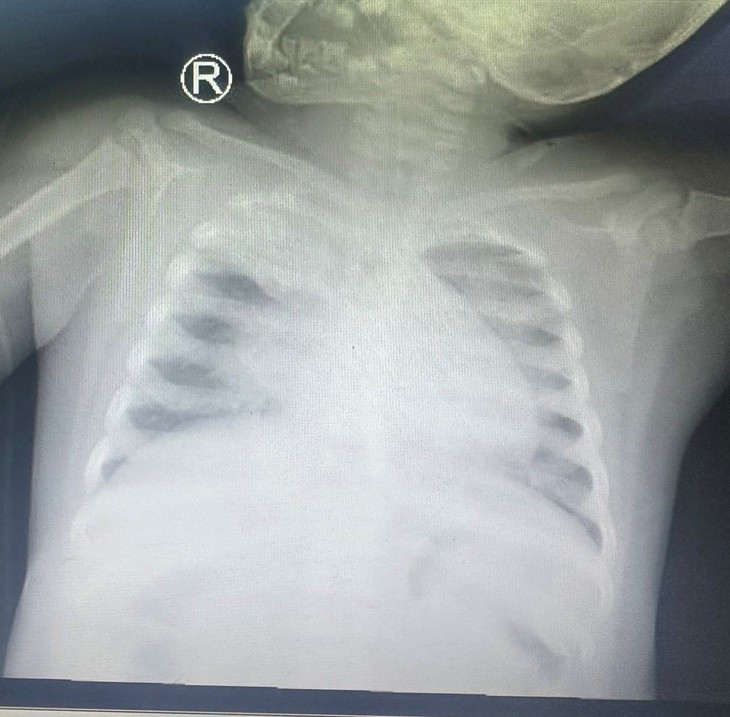

Cúm A là căn bệnh nhiễm trùng đường hô hấp cấp tính thường lưu hành khi thời tiết chuyển mùa, do các chủng virus cúm A phổ biến như A/H1N1, A/H3N2, A/H5N1, A/H7N9 gây ra. Trong đó, chủng A/H7N9, A/H5N1 lưu hành ở gia cầm và có nguy cơ lây sang người, trở thành dịch.

TS.BS Phạm Huy Tần, Bệnh viện Đại học Y Hà Nội, cho biết cúm A diễn biến nhanh, tiềm ẩn nhiều nguy hiểm và có thể bùng thành đại dịch. Bất kỳ ai cũng có thể mắc cúm A. Nhóm đối tượng dễ mắc và nguy cơ biến chứng nặng gồm người trên 65 tuổi, trẻ em dưới 5 tuổi, đặc biệt trẻ dưới 2 tuổi; người có bệnh nền huyết áp, tim mạch, bệnh phổi mạn tính; phụ nữ mang thai; người bị suy giảm miễn dịch (HIV, sử dụng corticoid kéo dài).